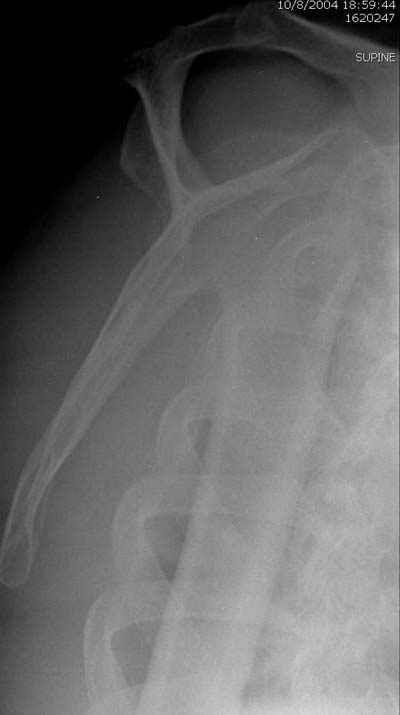

Re: Перелом шейки плеча

Андрей 25 Ноябрь 2004, 23:49

Женя, а как ты водишь спицы, в смысле, как делаешь входное отверстие, и как в него проводишь V-спицу? А то о дна из спиц, та, у которой не дошла до головки одна палочка буквы V, как-то выглядит на рентгенограмме, как будто или через очень большое отверстие введена, или каждая половинка через отдельные отверстия.

В чем ты видишь причину вторичного смещения?

Мне кажется, проблема в том, что не все концы спиц зашли в головку, и зашедшие - недостаточно далеко прошли.